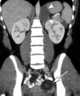

Ovarian cancer is a cancer that forms in or on an ovary. It results in abnormal cells that have the ability to invade or spread to other parts of the body. [Source: Wikipedia ]